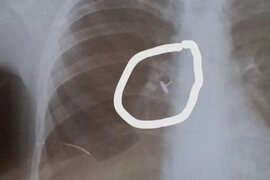

Azərbaycanda həkim yad cisim udan uşağa soyuqlama əleyhinə müalicə yazdı

Azərbaycanda həkim nəfəs borusunda yad cisim qalan uşağa soyuqlama əleyhinə müalicə yazıb. Ölkə.Az xəbər verir ki, bu iddia ilə pediatr Aytən İsmayılzadə çıxış edib. O, hadisənin Zaqatala rayonunda baş verdiyini bildirib:. "Uşaqdan gecələr yatanda qəribə səs gəlirmiş, öskürək, xışıltı narahat edirmiş